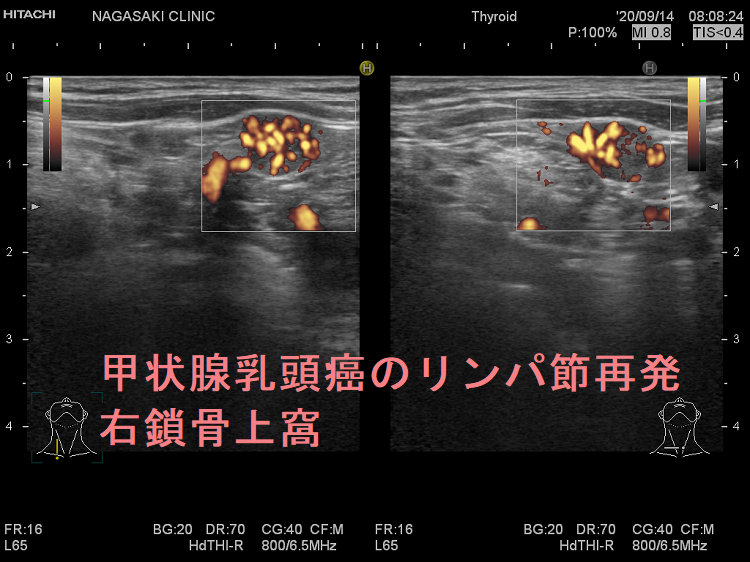

甲状腺乳頭癌鎖骨上窩リンパ節転移再発

甲状腺乳頭癌のリンパ節再発 右鎖骨上窩 超音波(エコー)画像

甲状腺乳頭癌のリンパ節再発 右鎖骨上窩 超音波(エコー)画像;いびつな形で、周囲との境界が一部不明瞭化して浸潤を疑われる。リンパ門は消失し、砂粒状石灰化を認める。

甲状腺乳頭癌のリンパ節再発 右鎖骨上窩 超音波(エコー)画像 ドプラーモード

甲状腺乳頭癌のリンパ節再発 右鎖骨上窩 ドプラーモード;内部に異常な走行の血管を認め、血流豊富。

甲状腺乳頭癌のリンパ節再発 右鎖骨上窩 超音波(エコー)画像(拡大)

甲状腺乳頭癌のリンパ節再発 右鎖骨上窩 超音波(エコー)画像(拡大);いびつな形で、周囲との境界が一部不明瞭化して浸潤を疑われる。リンパ門は消失し、砂粒状石灰化を認める。

甲状腺乳頭癌のリンパ節再発 右鎖骨上窩 超音波(エコー)画像 ドプラーモード(拡大)

甲状腺乳頭癌のリンパ節再発 右鎖骨上窩 ドプラーモード(拡大);内部に異常な走行の血管を認め、血流豊富。